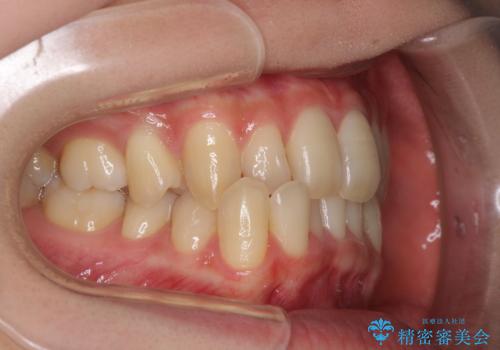

奥歯の反対咬合 上顎骨を拡大してインビザラインで矯正

- 奥歯の反対咬合を気にして来院された患者様です。

反対咬合は上顎骨の幅が下顎骨よりも小さいことが原因なので、拡大装置により骨幅を広げて上下関係を改善し、その後インビザラインにて歯並びを整えることとしました。

反対咬合が改善され、食いしばり癖もなくなり、顎関節の負担が軽減されました。

上顎骨を拡大したことで前歯に隙間ができ、1ヶ月ほど恥ずかしい時期がありましたが、しっかりとした咬み合わせに仕上がり、患者様には大変満足していただきました。